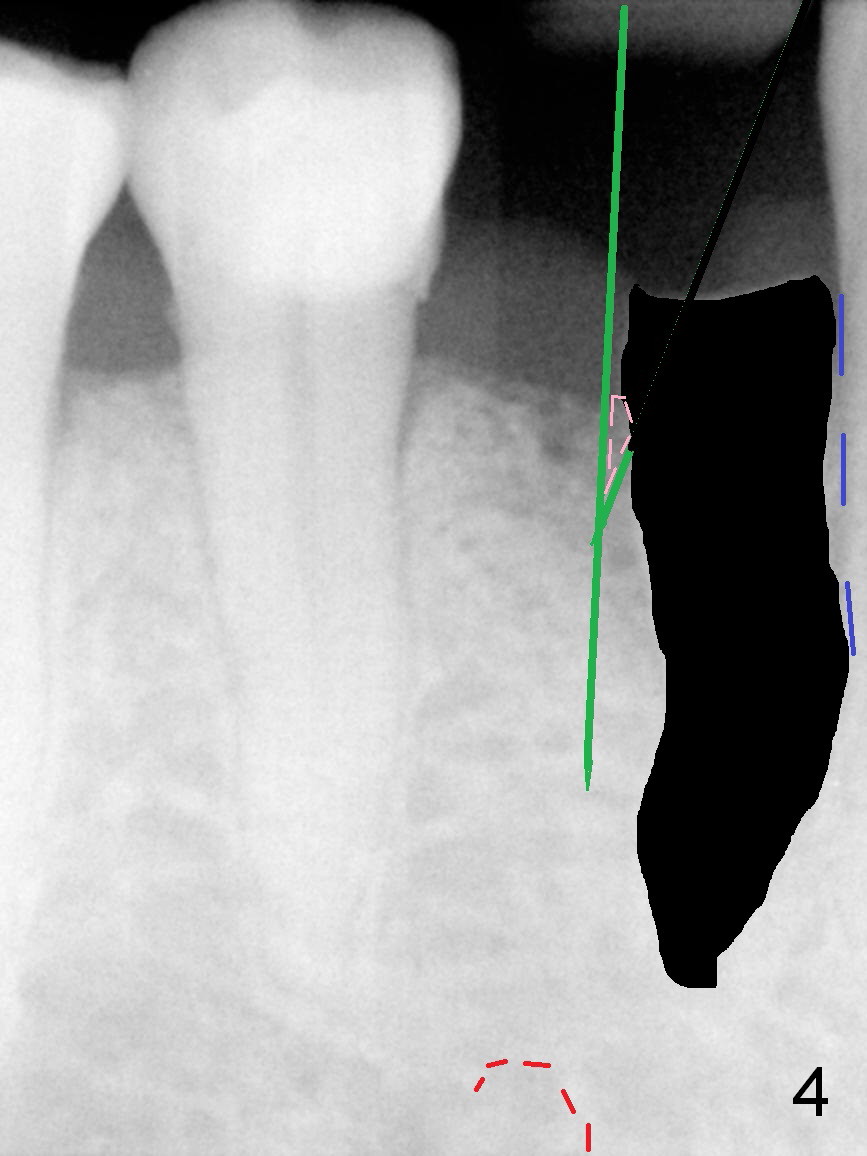

A 73-year-old man requests extraction of the lower right 1st premolar and implant restoration (Fig.1: #28). The root of the affected tooth (Fig.2 black area) is not only curved, but also deviated mesially (close to the root of the canine (blue dashed line). Osteotomy should be established with a sharp 1.5 mm pilot drill obliquely in the distolingual slope of the socket (treated with Metronidazole, Fig.3 (green line)). Once bony penetration is obtained, the drill straightens up in the middle of the socket and along the ideal long axis (Fig.4). Remove the bone in between (Fig.4 pink dashed line) if there is resistance to change in the trajectory. A PA is taken to confirm the position and trajectory. Then extend the osteotomy (Fig.5 green line) , but not beyond the apices of the neighboring tooth and the original socket (brown line), since the Mental Loop is nearby (Fig.2-5 red dashed line).